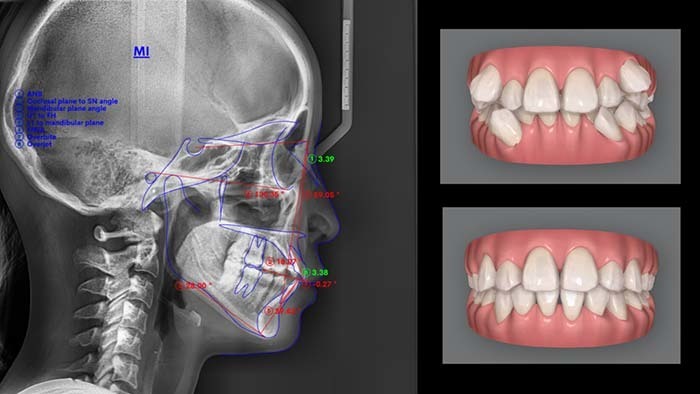

1,800症例(※)を手がける中で培った経験と、歯科用CTやセファロといった精密な検査機器を活用しながら、一人ひとりに合わせた矯正治療をご提供いたします。

治療を希望される場合は、精密検査を実施。レントゲンやCT撮影、お顔やお口の中の写真撮影などを行い、骨格や歯の状態を3次元的診断します。

これらの検査結果に基づき、矯正担当医が適切な治療計画を立案。シミュレーション動画をお見せしながら、歯の動き方や正確な費用・期間についてお伝えします。